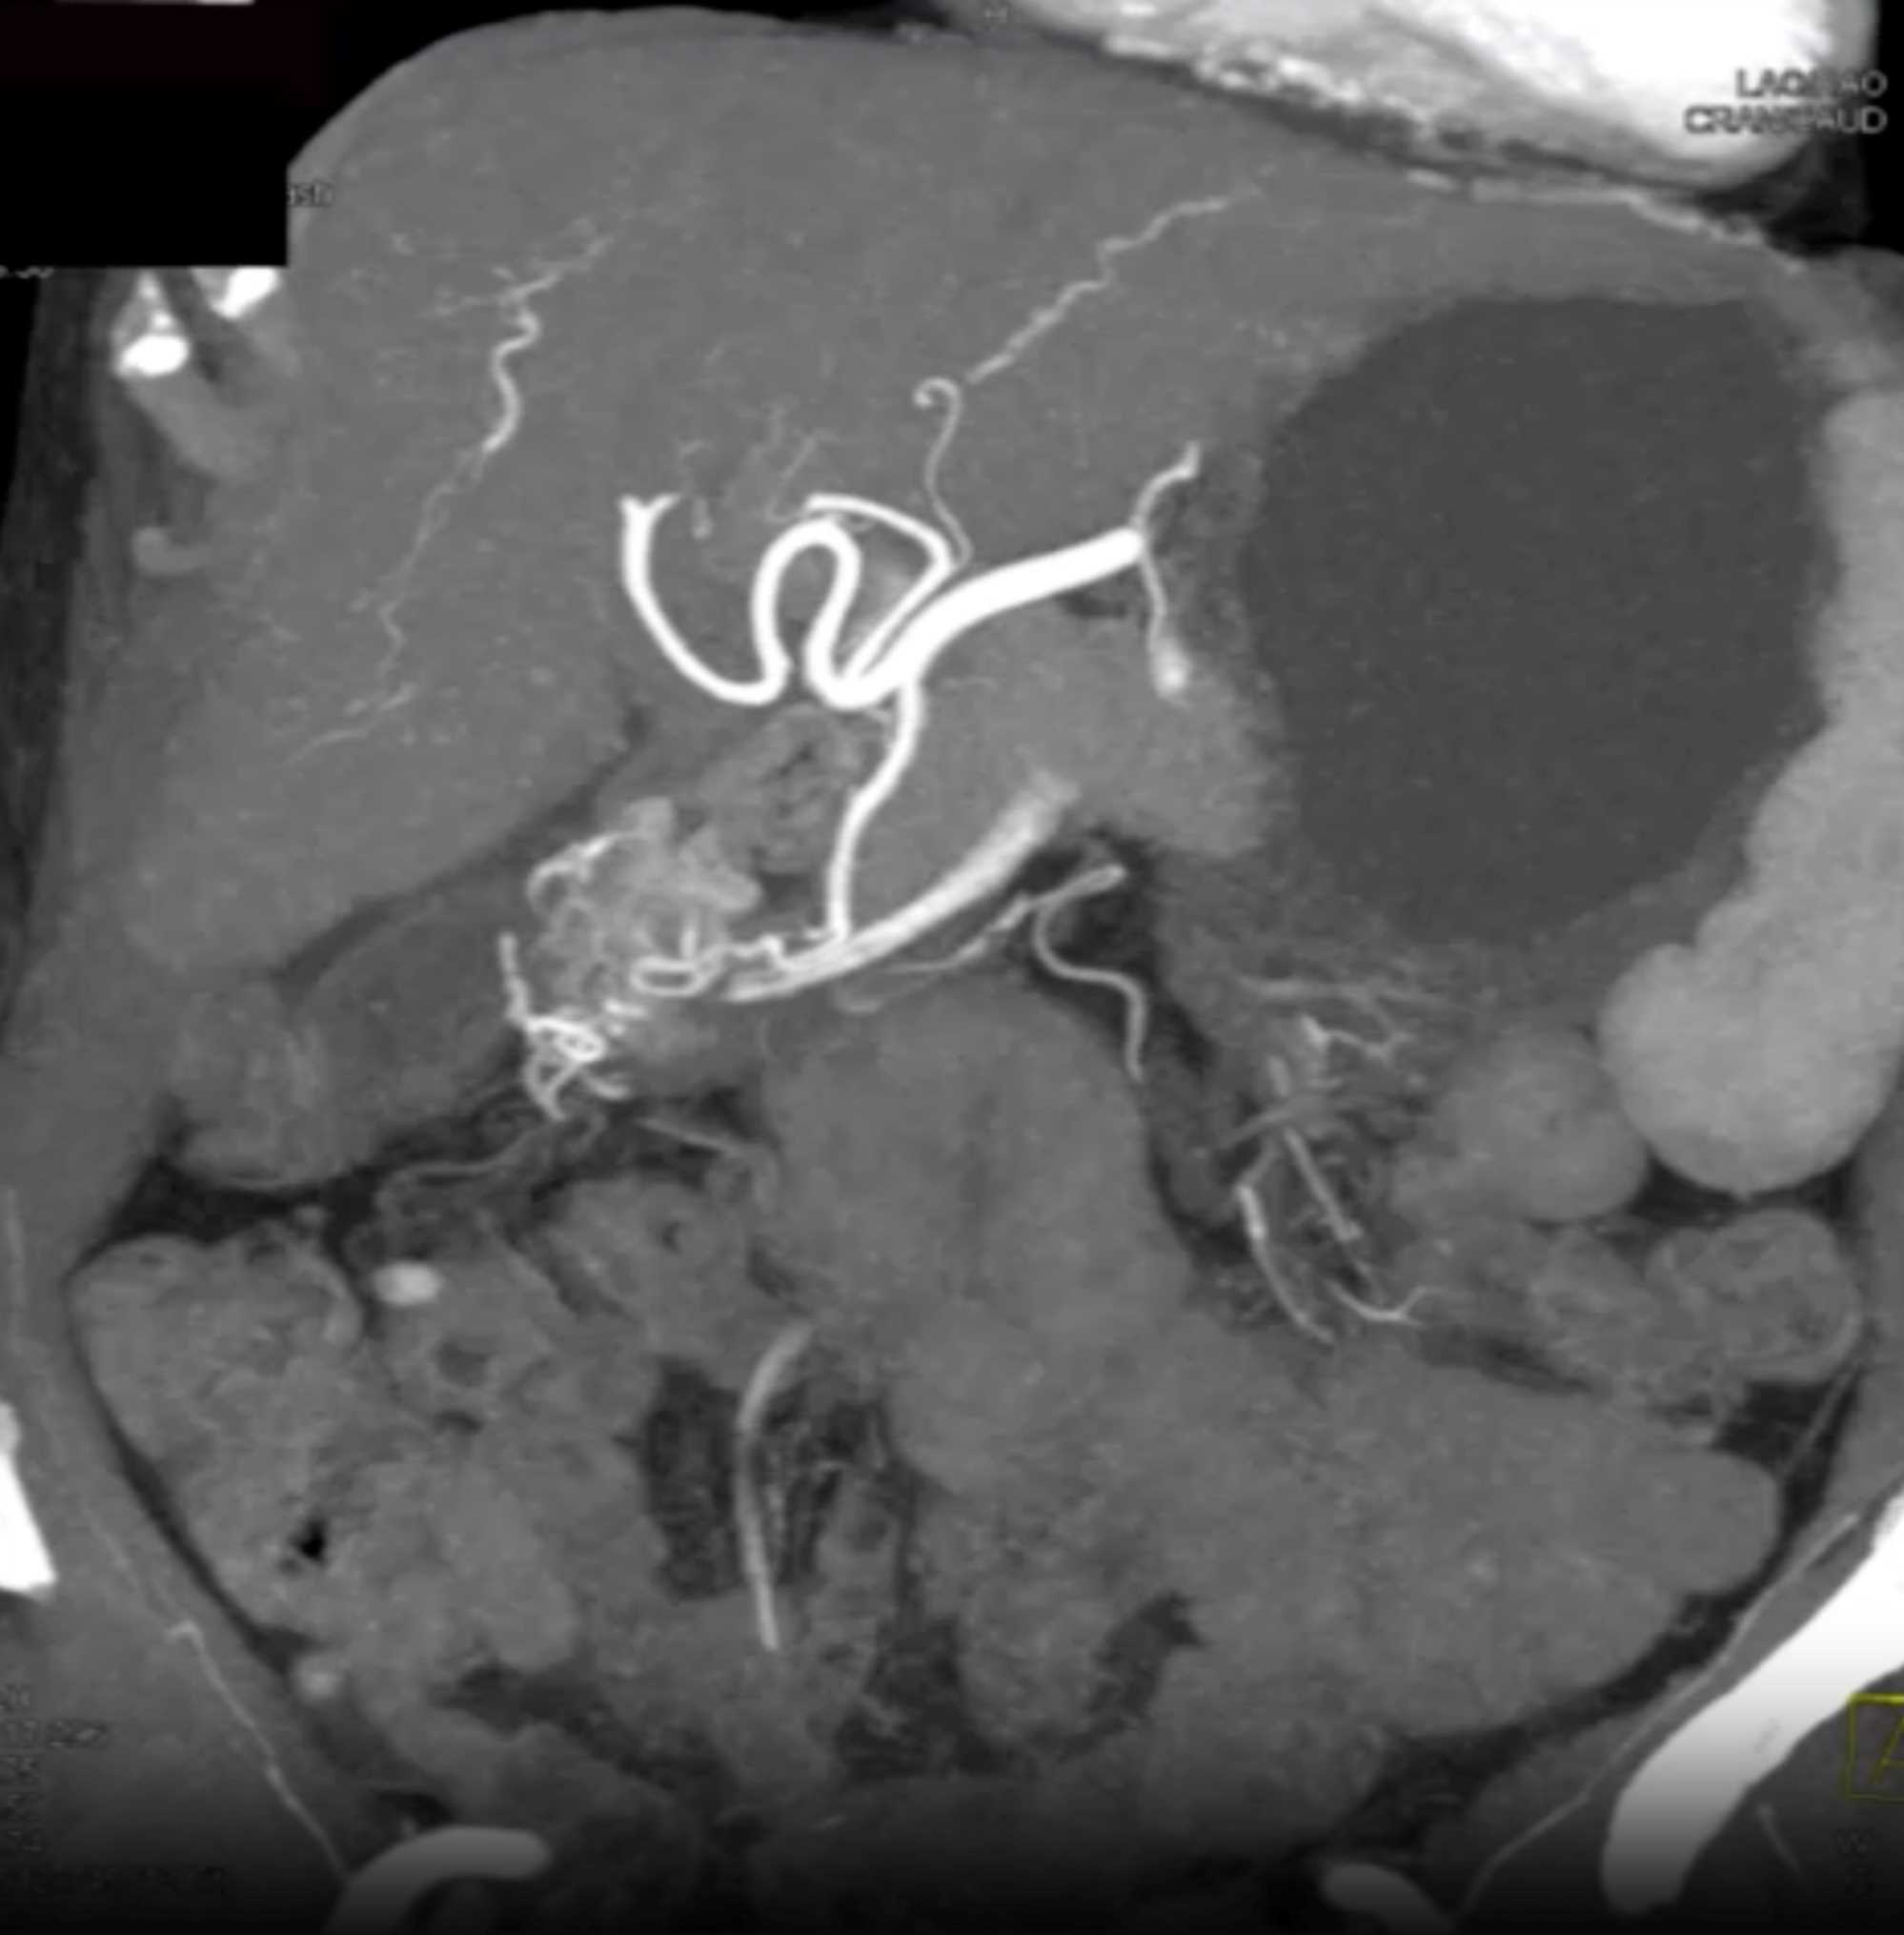

Watermelon Stomach (Gastric Antral Vascular Ectasis)